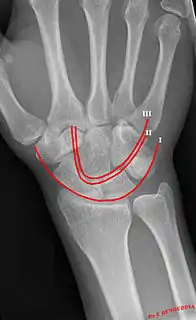

Gilula carpal arcs.

Gilula's lines are three arcs drawn on an AP radiograph of the wrist used to assess the alignment of the carpal bones.[1]

There should be no step-off in the contour of the lines when drawn on a normal wrist.

First arc | running along the proximal convexity of the scaphoid, lunate and triquetrum |

Second arc | running along the distal concavities of the scaphoid, lunate and triquetrum |

Third arc | running along the proximal curvatures of the capitate and hamate |